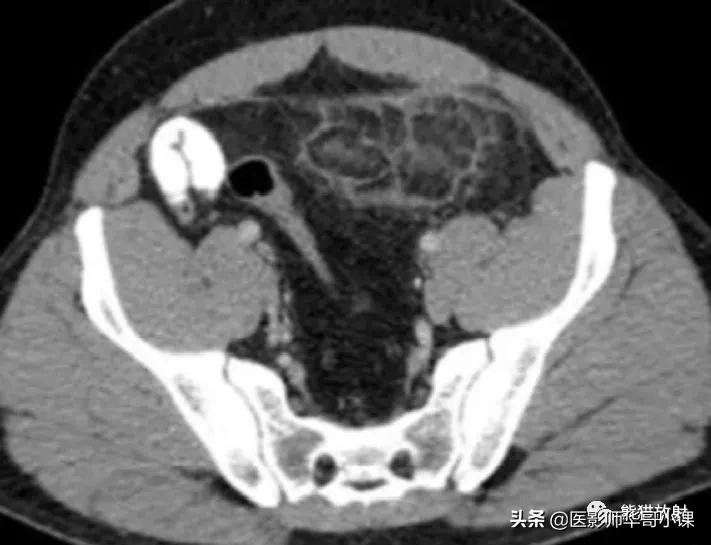

肠脂垂扭转或血栓症可以引起肠脂垂炎。临床表现与急性憩室炎或阑尾炎相似,大多数病例具有自限性。肠脂垂炎的CT表现有助诊断,从而避免不必要的手术。 最常见的CT表现 为直径 小于5cm 的卵圆形脂肪密度病变,与结肠浆膜面毗邻,周围呈炎性改变。肿块周围可见 高密度环形边缘,为炎性的脏层腹膜 (图)。病灶常含有血栓血管造成的高密度中央区。常见邻近结肠壁轻度反应性增厚。

肠脂垂炎。增强CT显示阑尾周围腹膜见一边缘呈高密度的脂肪灶,并周围炎症,位于乙状结肠前方。抗炎治疗后患者的症状减退。